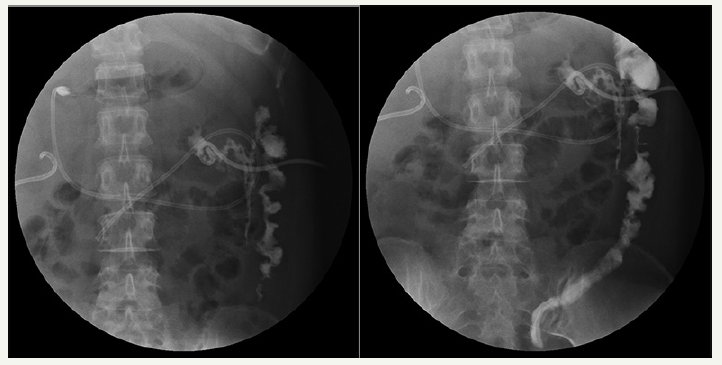

Figure 3:Fistulography via drainage tube showing the presence of a colonic fistula into the descending colon.

In June, she was admitted to our hospital because of persistent pyrexia. The laboratory data on admission showed that: white blood cell count (WBC) 16.11×10^9/L, C-reactive protein 67mg/L, which indicated the inflammatory reaction. Abdominal CT showed the presence of pancreatic pseudocysts and gall-bladder wall thickening (Figures 1 & 2), so percutaneous drainage was performanced. Yellow feculent liquid fluided from the drainage tubes. Thereby the bacterial, fungal culture and drug sensitivity experiments of the drainage were performanced. The result showed the presence of Enterococcus faecium, Pseudomonas aeruginosa, Enterobacter cloacae. Subsequently, fistulography via drainage tube showed the presence of a colonic fistula into the descending colon (Figure 3). Due to the unsatisfactory effect of conservative treatment, surgery was scheduled. The patient subsequently underwent transverse colostomy in August.